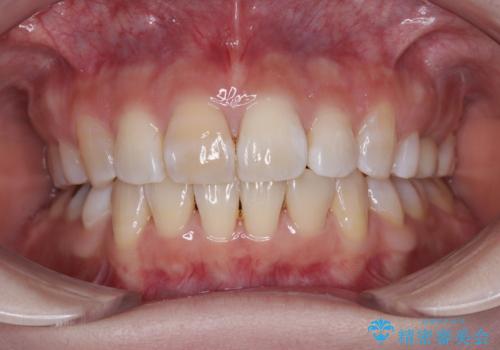

前歯のガタつきを改善 抜歯矯正後の後戻り

前歯を後ろに下げたい ワイヤー矯正(クリア装置)